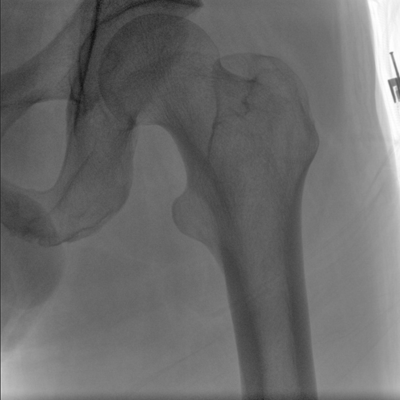

大尺寸動(dòng)態(tài)平板探測器,高DQE、低噪聲、圖像清晰。采用多分辨率圖像增強處理技術(shù),不同部位不同圖像處理算法,滿(mǎn)足客戶(hù)多樣化的需求。

采用智能變頻脈沖透視技術(shù),優(yōu)化圖像質(zhì)量的同時(shí)降低輻射劑量,呵護醫患健康

多角度自由旋轉,滿(mǎn)足患者復雜擺位需求。